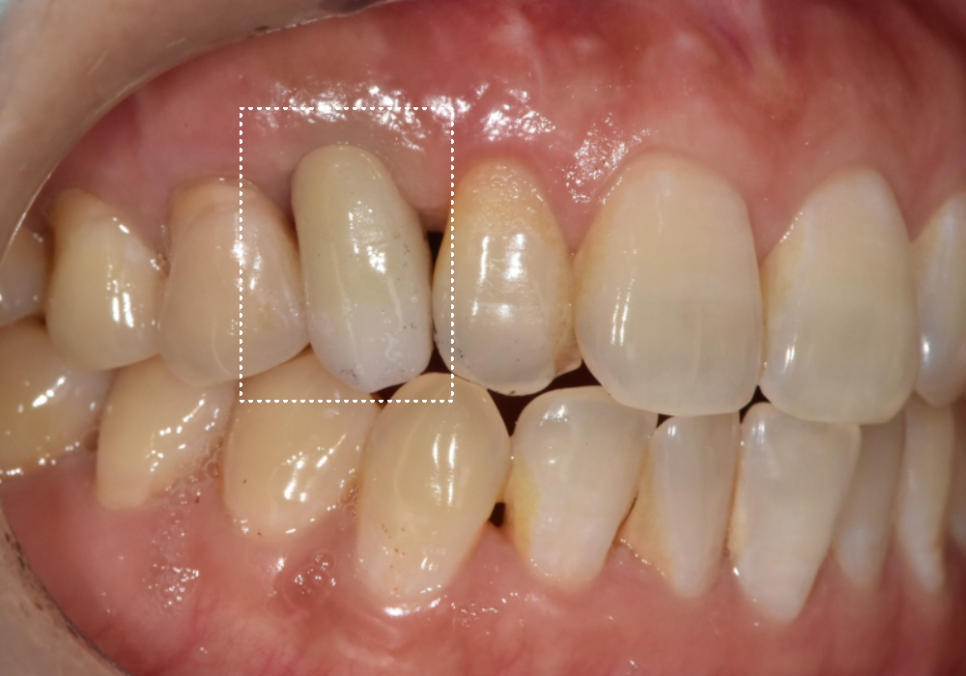

최근에 50년 동안 오른쪽 위 송곳니 자리에

유치(#53)를 간직해오신

환자분이 내원하셨어요.

이 부분이 유치인데,

확실히 다른 치아들보다 작은 느낌이 있죠?

잘 써온 유치가 최근 들어 조금씩 흔들리고

씹을 때마다 통증이 느껴져서 내원하신 건데요~